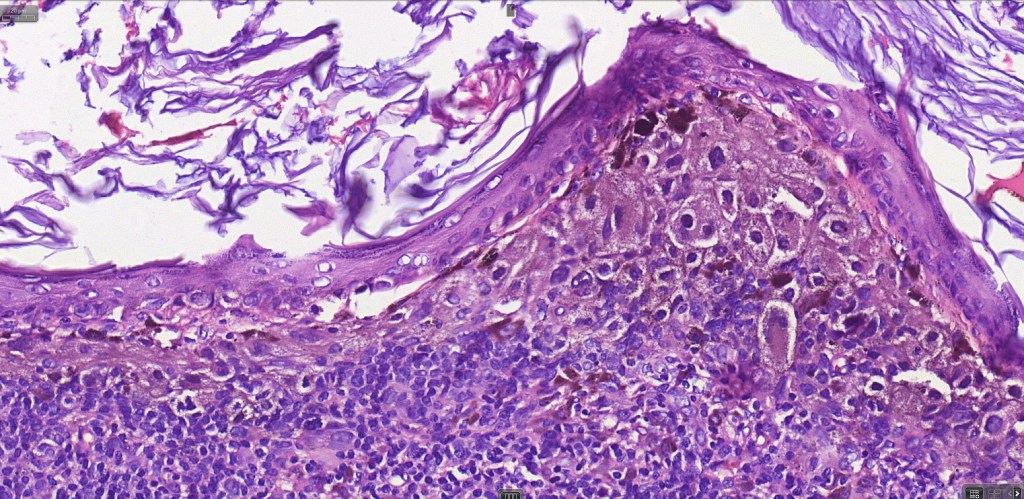

•Large dyscohesive nests with retraction artifact, not restricted to the tips of the epidermal ridges

•Heavy pigmentation (sometimes gray/green)

•Bridging common, often over multiple rete ridges

•Variable atypia (can be marked)

•Central pagetoid spread

•Superficial dermal atypia